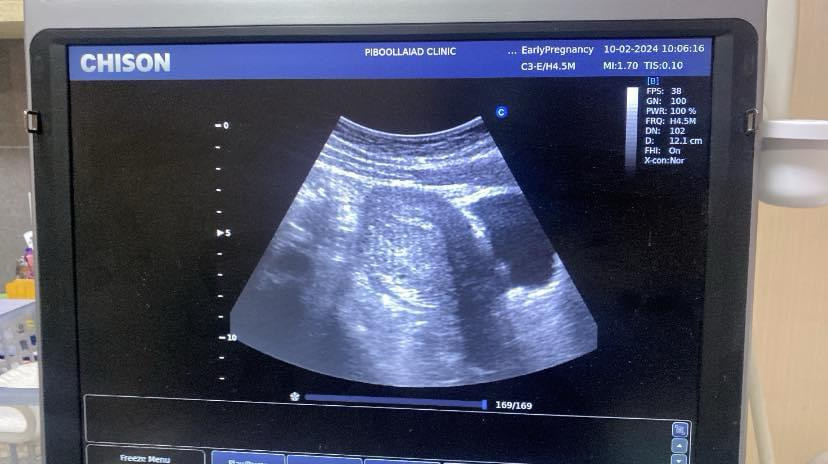

ไปซาวด์มาแล้วเจอรึยัง บ้านนี้ก็เจอแต่ถุงตั้งครรภ์ เป็นกำลังใจให้นะคะ

ปจด. ขาด ซื้อที่ตรวจมาขึ้น 2 ขีด แต่ไปหาหมอไม่เจอน้องค่ะ บอกแค่ว่าผนังมดลูกดูหนาขึ้น นัดใหม่อีกที 24กพ มีแม่ๆ ท่านไหนเป็นบ้างไหมค่ะ นอยมากๆๆเลยค่ะ แม่ใจฝ่อมากก กลัวไม่เจอน้องค่ะ🥺

เหมือนกันเลยคะซาวด์เจอถุงกับถุงที่ใช้เลี้ยงอาหารตัวอ่อน

ตอน6สัปดาห์ก็เจอเล็กมากๆๆค่ะ หมอนัดอีกที19นี้ค่ะ ซาวอีกครั้ง ไม่รู้จะเจอไหมค่ะ แต่หมอบอกว่า ท้องในมดลูกคะ